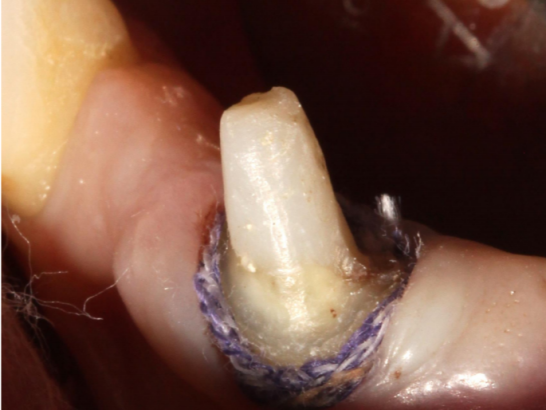

Step 2: Place the first retraction cord in the gingival sulcus

The model of the gingival retraction cord should be based on the ability to fill 1/2 of the gingival sulcus. The first retraction cord can help protect the gingival tissue from damage and also help identify the junctional epithelial attachment site.

Step 4: Place the second retraction cord in the gingival sulcus

Choose a retraction cord that fills the gingival sulcus. It can be observed that the retraction cord completely surrounds the tooth. The second retraction cord often needs to be impregnated with hemostatic material.